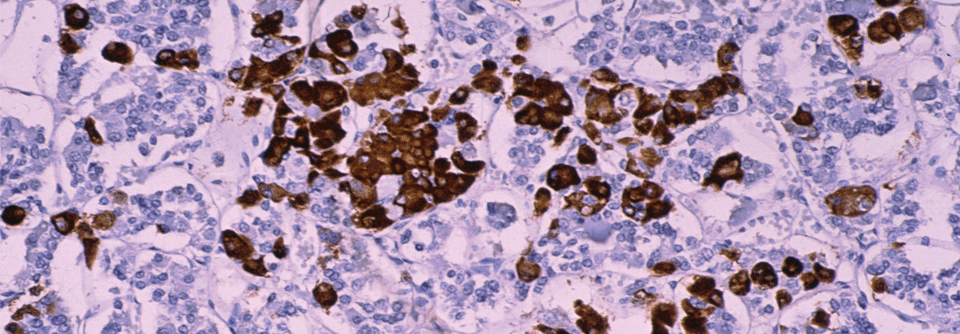

Je nachdem, aus welchem Zelltyp sich ein Hypophysenadenom entwickelt, kann es völlig unterschiedliche Beschwerden verursachen – oder gar keine. Zwar sind die Geschwülste gutartig. Dennoch können sie lebensgefährlich werden.

Hypophysenadenome kommen gar nicht mal so selten vor – Schätzungen gehen von einer Prävalenz von 1:1000 aus, erklären die Endokrinologin Dr. Aparna Pal vom Oxford Center for Diabetes, Endocrinology and Metabolism der Universitätskliniken Oxford und ihre Kollegen. Rein statistisch, befindet sich also auch in Ihrer Praxis mindestens ein Betroffener.